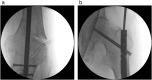

Bone healing is a complex and well-orchestrated physiological process, in which bone repairs and regenerates regaining its original biomechanical and biochemical properties. It is estimated that 5 to 10% of all fractures are complicated by delayed union or non-union. Progression to non-union is thought to be multifactorial, even though the exact biological sequence remains obscure. Treatment should aim to addressing deficiencies in both the mechanical and biological components, along with eliminating co-factors that could negatively affect the locally induced fracture healing response. We report a case of a 78-year-old patient who presented with a distal femoral non-union above a previously fused knee, which was successfully managed with exchange nailing and intramedullary delivery of recombinant human bone morphogenetic protein-7 (rhBMP-7).